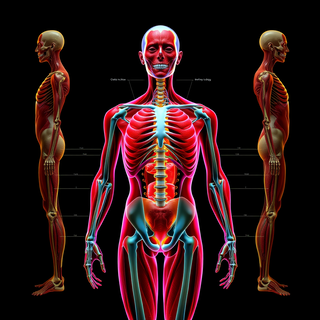

Generate ultra-realistic microscopic imagery for medical research.Open

Generate ultra-realistic microscopic imagery for medical research.Open